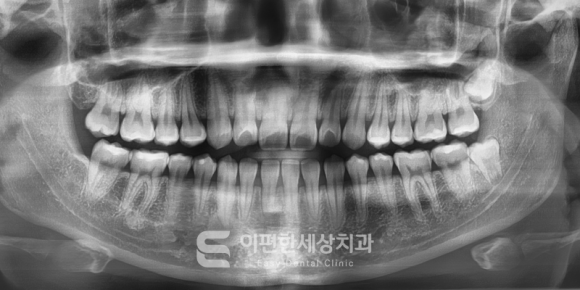

*이해를 돕기 위한 이미지 입니다.(파노라마 사진)

사랑니를 발치할 때 가장 기본적으로

진단하는 것이 바로 X-RAY입니다.

파노라마 방사선 사진이라고 부르는데,

이 진단은 매우 유용한 초기 진단 방법이죠.

치열의 전체적인 구조, 골 구조, 인접 치아와의 관계,

대략적인 뿌리의 형태 등을 한눈에 파악할 수 있는

중요한 진단 방법입니다.

또한 비용이 비교적 저렴하고

방사선 노출이 적으며 촬영이 간단하다는 장점도 있죠.

하지만 파노라마 사진만으로는

확인이 어려운 부분이 있습니다.

파노라마의 경우 2차원, 단편적인 진단 방식이기 때문에

깊이, 입체감, 정확한 거리 정보는

다소 부족한 편입니다.